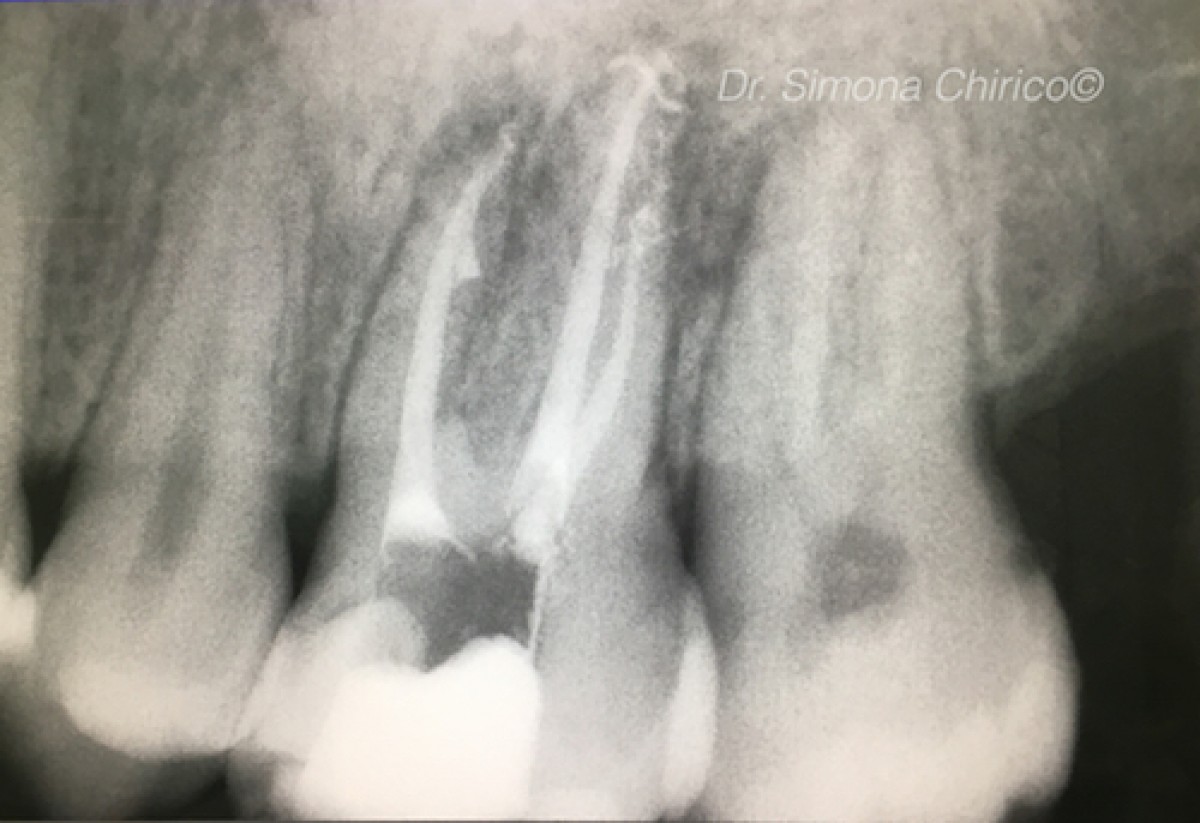

Nickel Titanium vs M-Wire vs Gold Wire: which guarantees the best root canal shaping?

In these years, different kind of rotary instruments were created for root canal shaping. The aim of using these instruments was to create a correct tapered shaped canal in order to respect the original canal anatomy and avoid canal transportation, ledge formation and perforations. Rotary instruments can be of different wire: Nichel Titanium, M-Wire, Gold-wire.

The study published in the Journal of Endodontics by Van Der Vyver et al tried to answer this question. In fact, the aim of this study was to was to evaluate the root canal shaping effect of instruments manufactured from nickel titanium, M-Wire, and Gold wire with different glide path preparation techniques

135 mesiobuccal canals of extracted human maxillary molars were randomly divided into 3 equal groups (N = 45) for glide path preparation with K-files (KF) (Dentsply Sirona, Ballaigues, Switzerland), One G (OG) files (Micro-Mega, Besanc ̧on, France), and ProGlider (PG) files (Dentsply Sirona). Specimens of each glide path group were further divided equally into 3 groups for instrumentation with ProTaper Next (PTN, Dentsply Sirona), One Shape (OS, Micro-Mega), and WaveOne Gold (WOG, Dentsply Sirona) systems (n = 15). Micro–computed tomographic imaging was used to scan teeth before instrumentation and after shaping to compare centering ratio and canal transportation values at the apical, midroot, and coronal levels and the overall changes in canal volume. Data sets were statistically analyzed (analysis of variance and Kruskal-Wallis H tests).

Apical canal transportation was recorded, in particular, in the groups with the combination of K-file plus One Shape (K+OS) and K-file plus Protaper Next (K+PTN) (P = .003).

Mid-root canal transportation was recorded in groups with the combination of: K-file plus Protaper Next (K+PTN), K-file plus One Shape (K+OS), and One G plus One Shape (OG+OS) (P = .0003).

Coronal canal transportation was recorded in groups with the combination of: k-file plus protaper next (K+PTN) and k-file plus One Shape (K+OS) (P = .011). The lowest canal volume changing was recorded in the group with the combination of Proglider and WaveOne Gold (PG+WOG); the highest in the groups with Protaper Next (PTN).

Proglider with the WaveOne Gold can guarantee the best preservation of root canal

structure and volume during the shaping. This isn't the same when we use K-file with nickel titanium instruments or M-wire instruments, which remove more dentin from the canal walls.

(Photocredit: Dr. Simona Chirico)